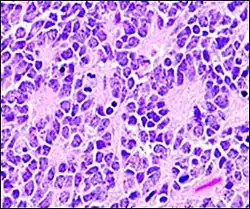

Perivascular pseudorosette

A perivascular pseudorosette consists of a spoke-wheel arrangement of cells with tapered cellular processes radiates around a wall of a centrally placed vessel. The modifier “pseudo” differentiates this pattern from the Homer Wright and Flexner-Wintersteiner rosettes, perhaps because the central structure is not actually formed by the tumor itself, but instead represents a native, non-neoplastic element. Also, some early investigators argued about the definition of a central lumen, choosing “pseudo” to indicate that the hub was not a true lumen but contained structures. Nevertheless, this pattern remains extremely diagnostically useful and the modifier unnecessarily leads to confusion. Perivascular pseudorosettes are encountered in most ependymomas regardless of grade or variant. As such, they are significantly more sensitive for the diagnosis of ependymomas than true ependymal rosettes. Unfortunately, perivascular pseudorosettes are also less specific in that they are also encountered in medulloblastomas, PNETs, central neurocytomas, and less often in glioblastomas, and a rare pediatric tumor, monomorphous pilomyxoid astrocytomas.[2]

Micrograph of perivascular pseudorosettes -